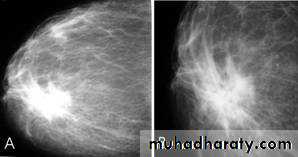

Ca breast

A…..Invasive ductal carcinoma is a subset of ductal carcinoma. It is an infiltrating, malignant and abnormal proliferation of neoplastic cells in the breast tissues. It is the most frequently seen breast malignancy .

Radiographic features

Mammogram

spiculated hyperdense lesion

oval/lobulated lesion

microcalicifications

Infiltrating or invasive lobular carcinoma (ILC) of the breast is the second most common type of invasive breast cancer after invasive ductal carcinoma (IDC) .

ILC is more often multicentric and bilateral (10-15%). Therefore imaging evaluation of the contralateral breast is crucial. There can be very subtle changes such as progressive shrinkage or enlargement or reduced compressibility of the involved breast. Imaging often underestimates the disease.

Mammography

The sensitivity of mammography for the detection of ILC reportedly ranges between 55-80% 8. Because of the limitations of mammography in detecting ILC, other modalities, such as sonography and MR imaging, are being used in evaluating clinically suspicious findings and known cancers to assess the extent of disease. ILC are more commonly seen on the craniocaudal (CC), compared to the mediolateral oblique (MLO).